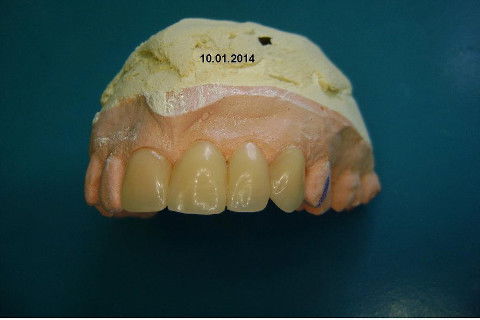

Paciente apareceu em meu consultório em dezembro/2013 para resolver problema de insatisfação com ponte fixa provisória anterior, realizada há 9 anos atrás (2004)...pretendia realizar somente a reabilitação em maxila/anterior, não contava com outros problemas com maior gravidade na sua boca, o máximo que citou foi a indicação para a exodontia do 16...

Cirurgia realizada hoje de manhã...No planejamento percebi medindo espessura do rebordo com especímetro que as medidas não estavam muito boas, ou o ideal, em torno de 4,5 a 5 mm ate´o terço médio do rebordo e melhorava no final, com 6 a 7 mm. Optei então por uma pequena expansão usando os expansores rosqueáveis. Aconteceu uma pequena fenestração na hora da fixação dos implantes, especialmente na região do 22 que fraturou o início da tábua óssea, mas não me preocupei porque não foi mais do que 2 mm de fratura em direção apical, o implante ficou infraósseo e com boa estabilidade (60 N no 21 e 40 N no 22). Esta fratura tb não deixou osso completamente solto, foi do tipo galho verde, deixei em posição e suturei normalmente. Só não fiz e nem estava planejado carga imediata mesmo, mais pelo motivo da oclusão inadequada do caso.